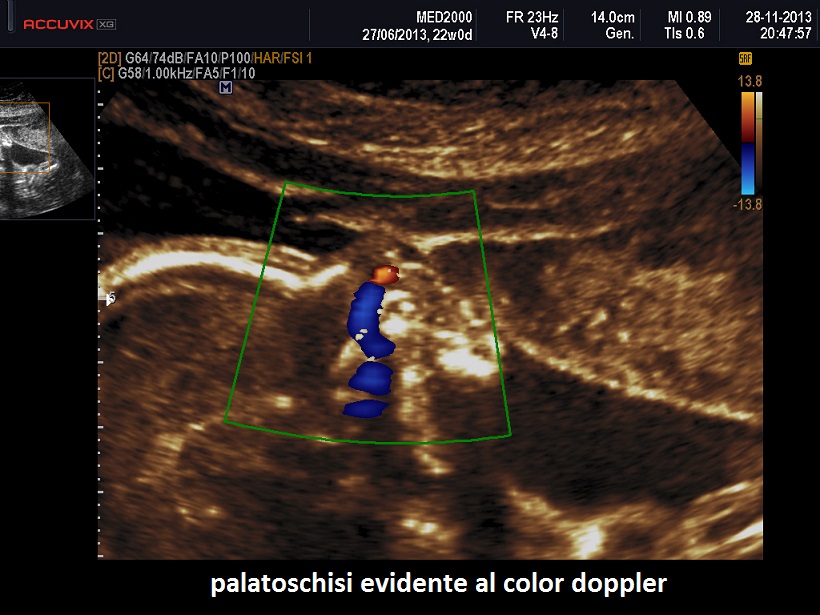

Così definita per le anomalie posturali e le contratture degli arti è una patologia generalizzata della cartilagine caratterizzata da distruzione della matrice cartilaginea, conseguente fibrosi e successiva ossificazione.

DIAGNOSI DIFFERENZIALE: si pone con l'artrogriposi dalla quale è facilmente riconoscibile per gli arti corti, il pollice da autostoppista ed i difetti del padiglione auricolare. Rispetto ad altre displasie scheletriche considerare che nelle displasia diastrofica le testa è sempre normale.

accurato studio ecografico